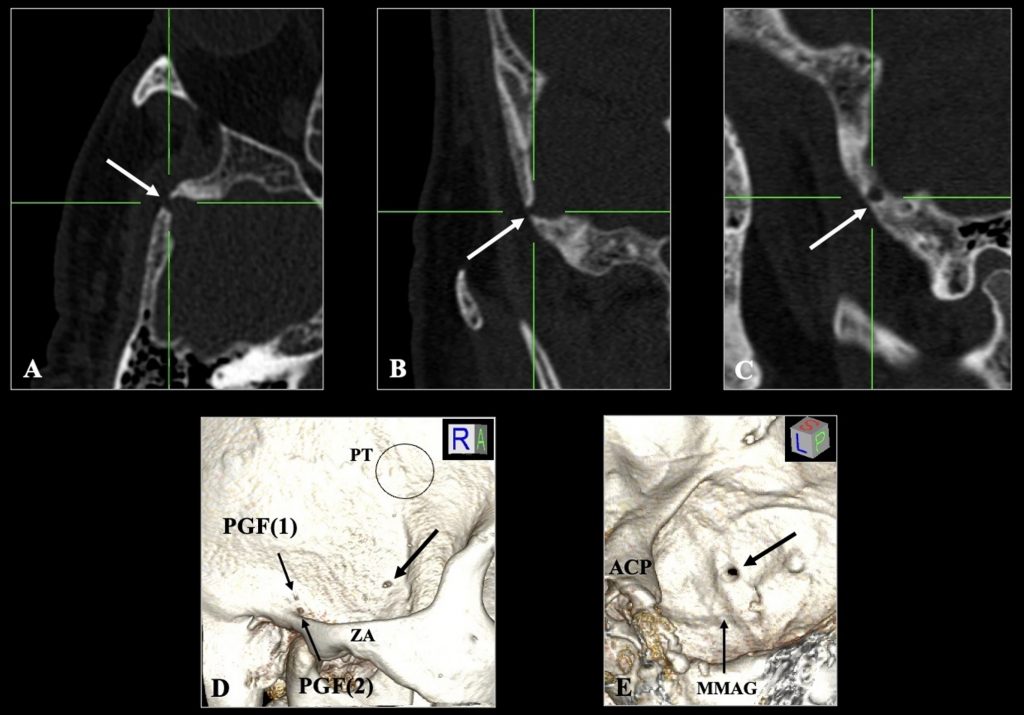

รูเปิดปล่อยเลือด (emissary foramen) เป็นช่องขนาดเล็กในกระดูกกะโหลกศีรษะที่เชื่อมต่อระบบหลอดเลือดดำภายในกะโหลกกับเครือข่ายหลอดเลือดดำภายนอก ทั้งนี้รูเปิดปล่อยเลือดที่พบบ่อยได้รับการอธิบายอย่างดีแล้ว แต่ความแปรผันที่ผิดปกติยังไม่ได้รับความสนใจเพียงพอ การศึกษานี้รายงานกรณีรูเปิดปล่อยเลือดที่ไม่ปกติในกระดูกข้างขมับของผู้ป่วยชายอายุ 64 ปีจากภาพถ่ายเอกซเรย์คอมพิวเตอร์ความละเอียดสูง พบช่องเปิดขนาด 3.15 มม. ที่แยกออกจากโพสท์เกลนอยด์ฟอราเมนและไม่พบในฝั่งตรงข้าม โดยตำแหน่งของรูเปิดนี้มีแนวโน้มแสดงการเชื่อมต่อหลอดเลือดดำจากพีทีรอยด์เวนัสเพล็กซัสสู่ช่องหลอดเลือดดำภายในกะโหลก การรับรู้รูเปิดที่ผิดปกติประเภทนี้มีความสำคัญต่อการตีความภาพทางการแพทย์ ป้องกันการวินิจฉัยผิดพลาด และเตรียมการผ่าตัดฐานกะโหลกศีรษะอย่างรอบคอบเพื่อหลีกเลี่ยงภาวะแทรกซ้อนเช่นเลือดออกโดยไม่คาดคิด

Citation: Triantafyllou, G., Papadopoulos-Manolarakis, P., Suwannakhan, A., & Piagkou, M. (2025). An unusual emissary foramen of the temporal bone. Surgical and Radiologic Anatomy, 47, Article 236. https://doi.org/10.1007/s00276-025-03753-2